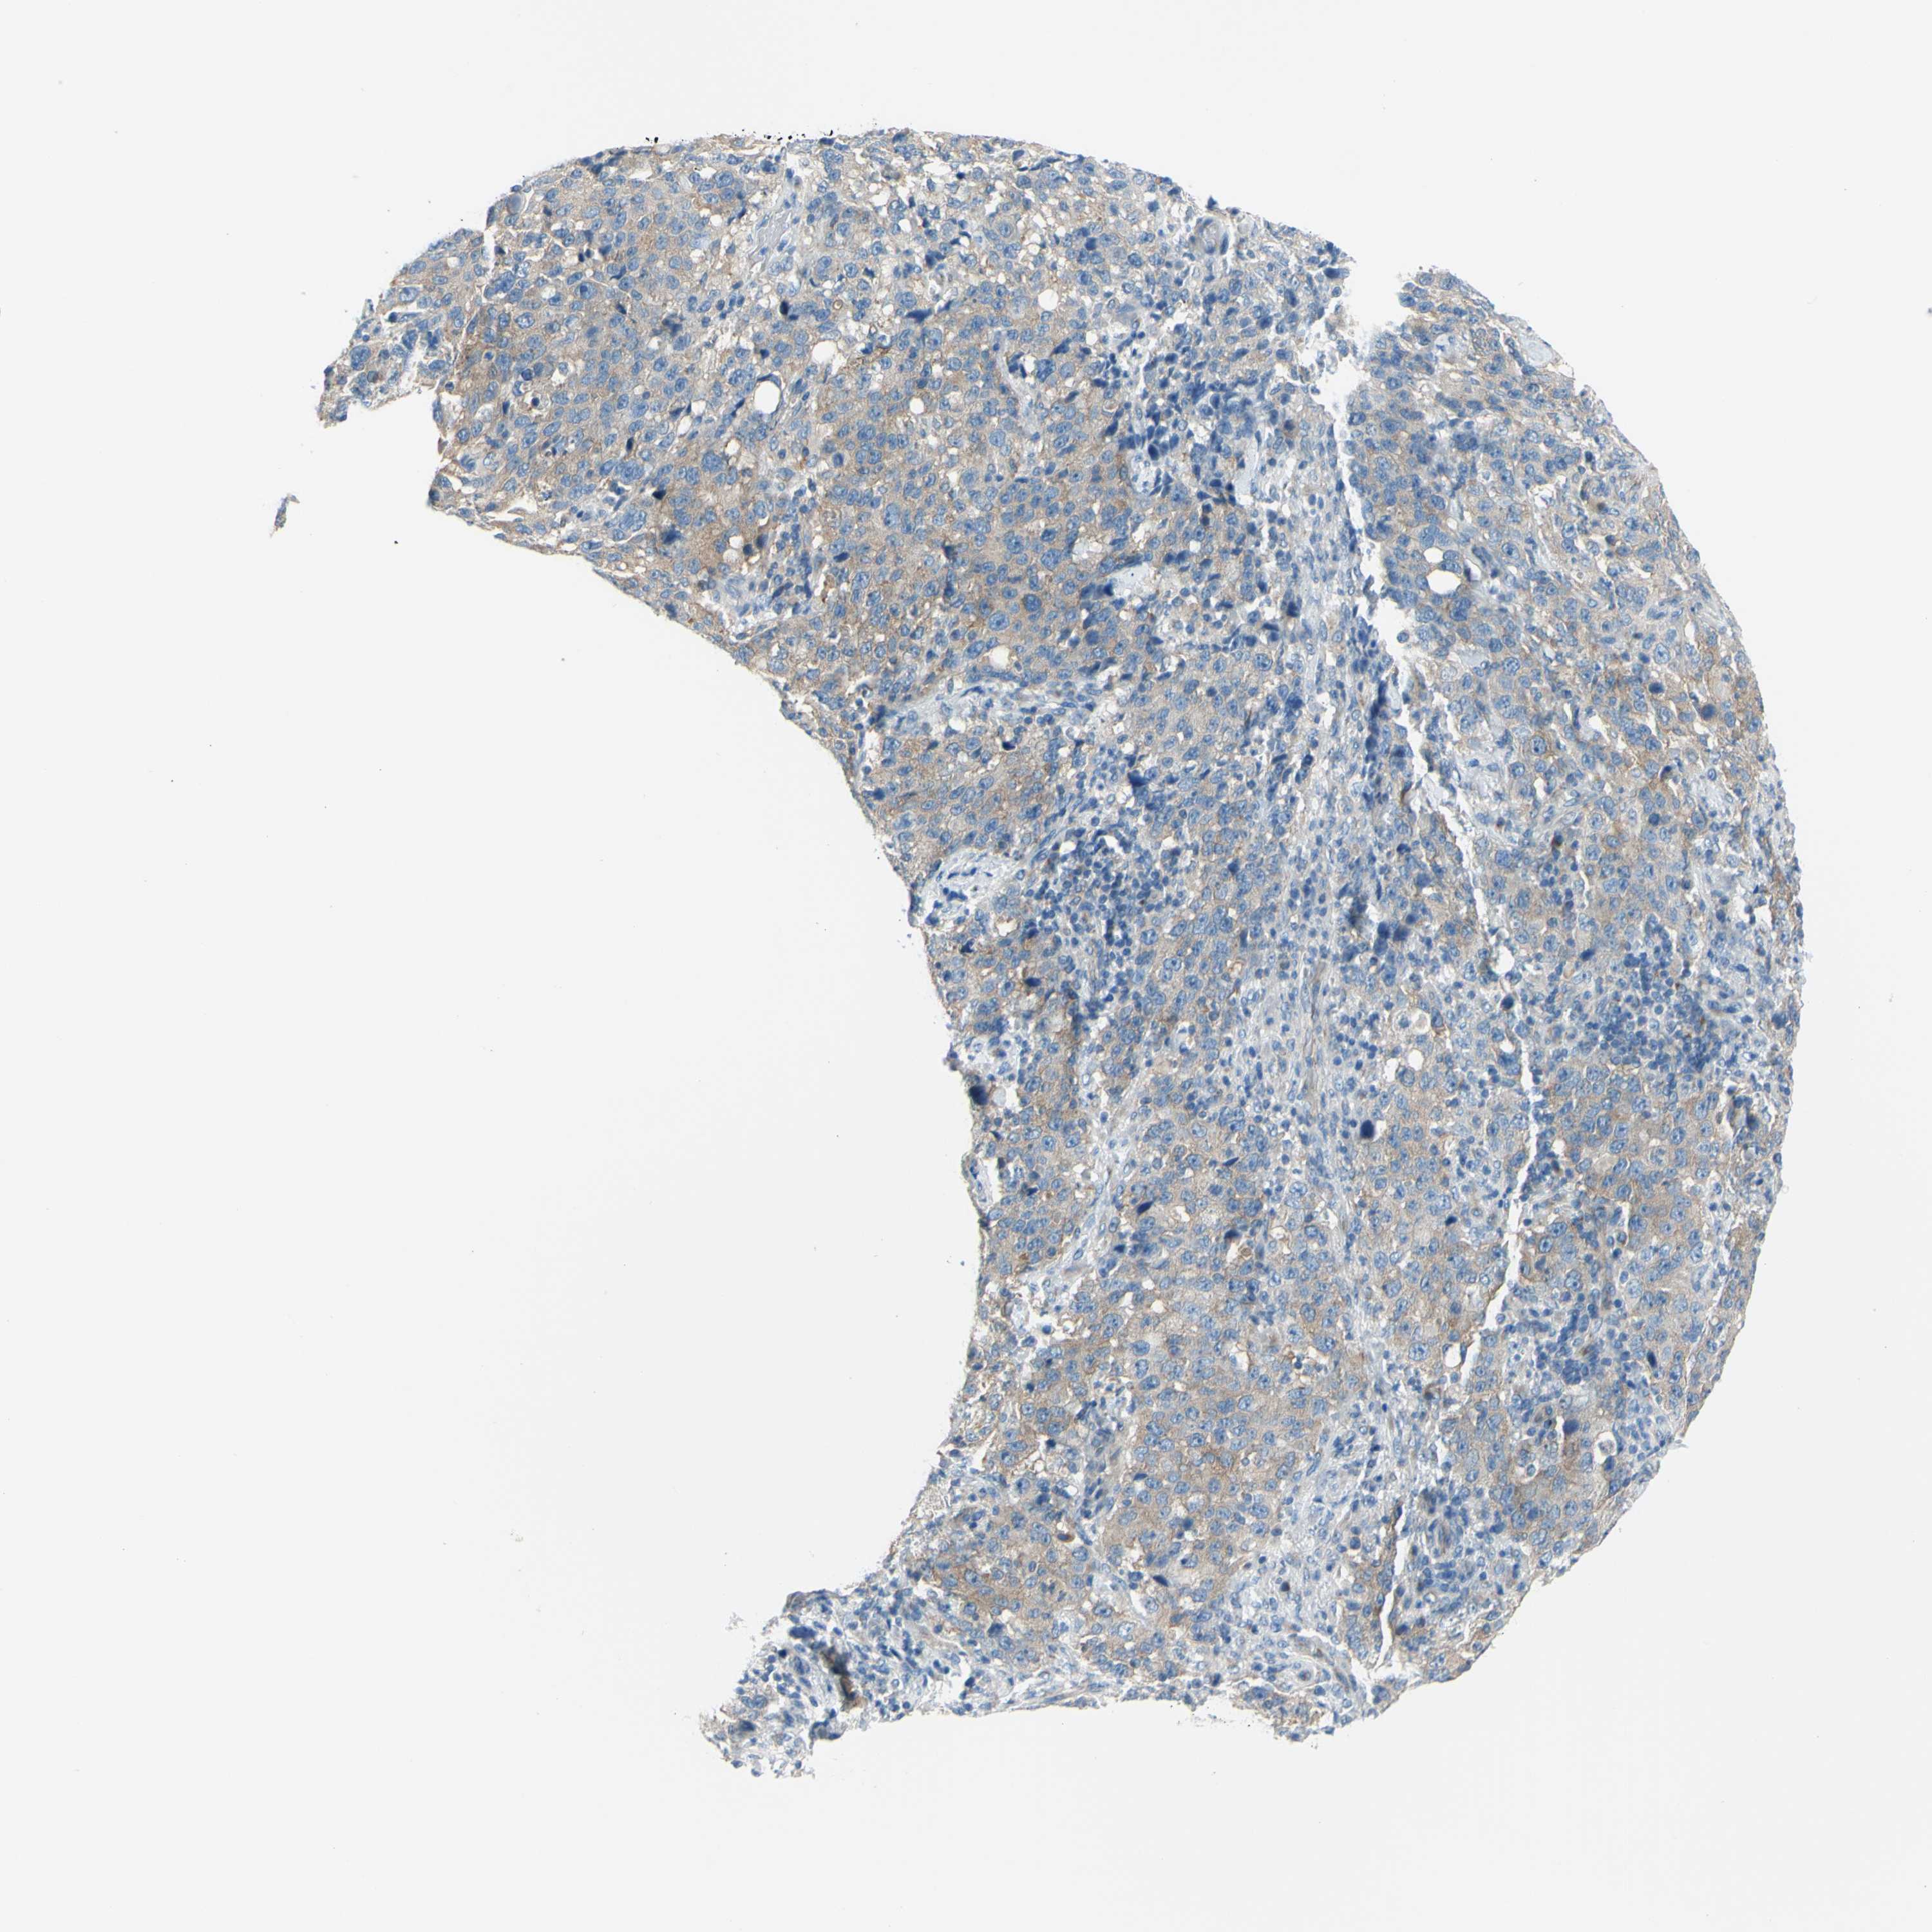

STOMACH CANCER - Protein expressioni

A mouse-over function shows sample information and annotation data. Click on an image to view it in a full screen mode. Samples can be filtered based on level of antibody staining by selecting one or several of the following categories: high, medium, low and not detected. The assay and annotation is described here.

Note that samples used for immunohistochemistry by the Human Protein Atlas do not correspond to samples in the TCGA dataset.

Antibody stainingi

Antibody staining in the annotated cell types in the current human tissue is reported as not detected, low, medium, or high, based on conventional immunohistochemistry profiling in selected tissues. This score is based on the combination of the staining intensity and fraction of stained cells.

Each image is clickable and will lead to virtual microscopy that enables deeper exploration of all samples and also displays staining intensity scores, fraction scores and subcellular localization as well as patient and tissue information for each sample.

Antibody HPA009705

Staining

High

Medium

Low

Not detected

Intensity

Strong

Moderate

Weak

Negative

Quantity

>75%

75%-25%

<25%

None

Location

Nuclear

Cytoplasmic/membranous

Cytoplasmic/membranous,nuclear

Adenocarcinoma, NOS

Adenocarcinoma, High grade